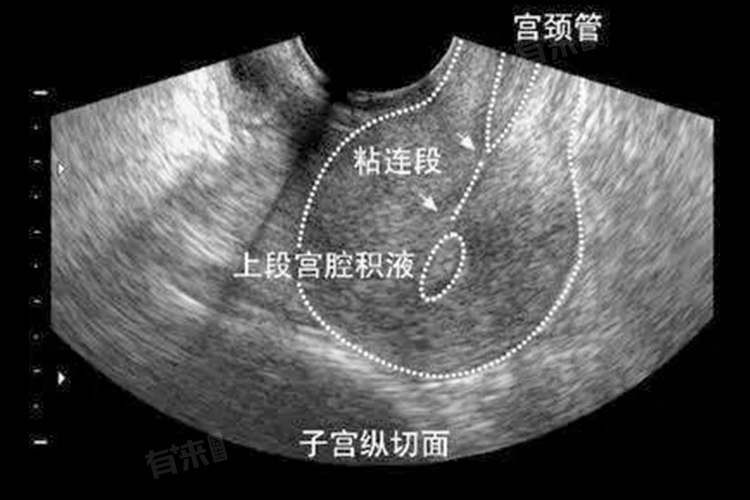

- 此时进行B超检查,超声波能够更清晰地穿透子宫内膜,准确显示子宫腔的形态结构。若存在宫腔粘连,其粘连部位、范围及程度在薄且均一的子宫内膜衬托下,更容易被识别。相较于月经周期的其他时段,此时的图像对比度更高,能有效提高诊断的准确性。

- 此外,在这个时间段内,子宫腔相对较为清洁,经血已基本排净,减少了因残留经血干扰超声图像的可能性。残留经血可能会在子宫腔内形成不规则回声,容易与宫腔粘连的异常回声混淆,从而影响医生对检查结果的判断。而在月经结束3至7天,子宫腔内环境相对稳定,为B超检查提供了更为理想的条件。